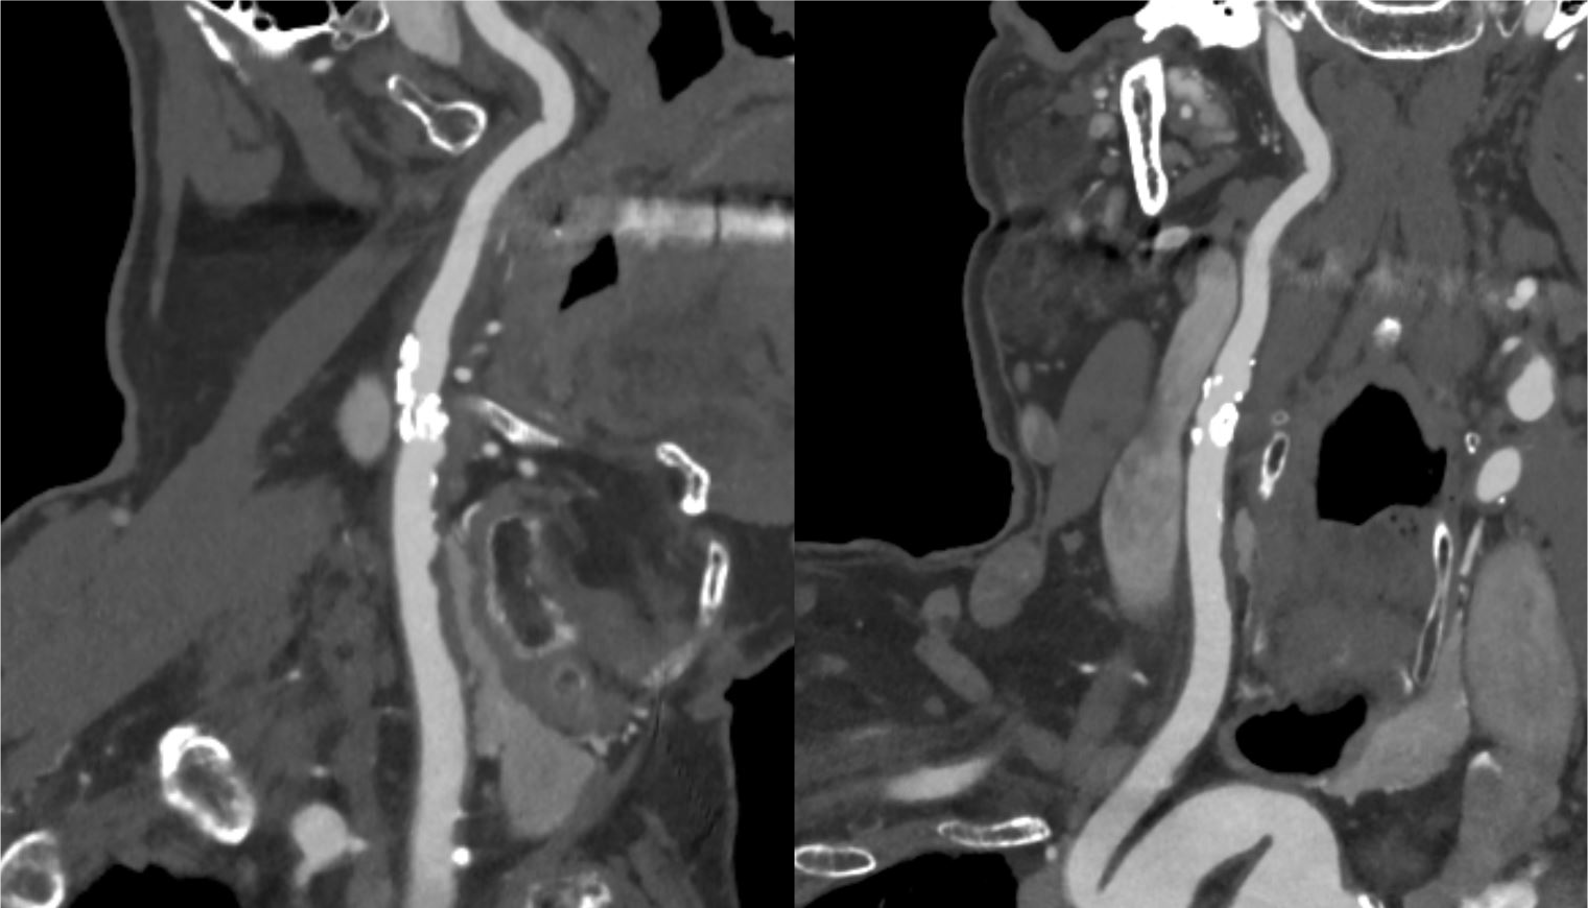

70歳代、男性、52kg、内頸動脈狭窄

右内頸動脈狭窄症の術前評価

2年前に左内頸動脈狭窄症に対して内膜剥離術施行後。今回、右内頸動脈狭窄の進行が疑われ、術前精査のためCT angiography施行。

内頸動脈狭窄症において、造影CTはMRIと並んで必須の検査である。MRIが苦手とする石灰化の評価、薄いスライス厚での狭窄率評価が、造影CTでは行いやすい。動脈相での評価が望ましく、血管内と血管外の境界が可能な限りシャープである方が、狭窄率の評価が行いやすい。

CT技術や撮像プロトコル設定について

Virtual Monoenergetic Imageで高エネルギー側の表示をすることで、金属アーチファクトを低減できたり、今回の症例のように、Iodine mapを用いることでヨード濃度を推定することができたり、Purelumen画像でCaなどの石灰化を除去することで、内腔の表示をより明瞭化する技術がある。シャープネスの高い動脈相の画像が望ましく、ヨード量は600mgI/kgは維持できるように気をつけている。